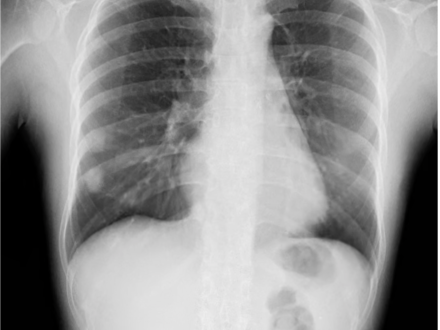

Wayne, NJ, March 7, 2023 – Konica Minolta Healthcare Americas, Inc., congratulates the University of Alabama at Birmingham (UAB) Hospital for achieving the significant milestone of imaging more than 1,000 patients with Dynamic Digital Radiography (DDR) technology since it was installed in June 2021. DDR has been utilized in the Kirklin Clinic of UAB Hospital for pulmonary imaging in pre and post lung transplant, post heart transplant, after COVID infection, chronic obstructive pulmonary disorder (COPD) and lung cancer patients, as well as for evaluating diaphragm dysfunction. UAB Medicine is a leading lung transplant center and one of busiest in the US, with one-year patient and graft survival rates higher than national averages.

DDR is a radiographic technique that provides a series of individual digital X-ray images acquired at high speed and low radiation dose. These images provide diagnostic-quality views of anatomical structures in motion and the ability to visualize the dynamic interaction with physiological changes over time.

Satinder Singh, MD, FCCP, FNASCI, FSABI, Professor of Radiology & Medicine and Chief of Cardiopulmonary Radiology in the Department of Radiology at UAB, explains that “DDR is a viable replacement for chest fluoroscopy in the evaluation of diaphragm function. It provides good visibility of lung abnormalities and increases our diagnostic confidence. Based on our extensive evaluation and utilization of this technology, we have now transitioned to DDR instead of traditional chest fluoroscopy to evaluate an elevated diaphragm. All lung transplant patients currently receive a DDR exam as part of their pre-surgical workup.”

DDR provides enriched radiographic information and enhanced diagnostic capabilities. Compared to fluoroscopy, the patient’s radiation dose is lower with DDR, comparable to a standard two-view X-ray exam. Dr. Singh and his colleagues at UAB use DDR to routinely assess diaphragm function in transplant patients and, in some cases, monitor treatment effects, examine airways and evaluate pulmonary function in their patients.